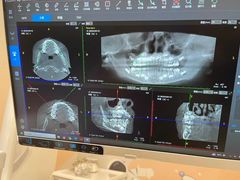

• 德伦口腔(海珠总院)

• -德伦口腔(海珠总院)